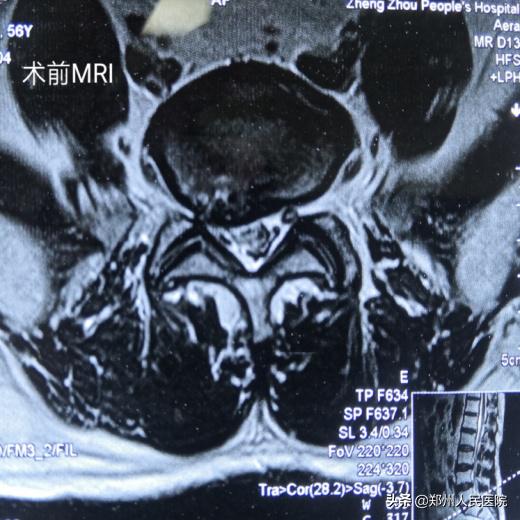

56岁的刘叔有着和小葛一样的困扰,而且他的症状更严重,病程时间更长。腰部疼痛伴右下肢放射痛麻木8年,加重伴间歇性跛行1个月,右足跟、足底及足外侧的皮肤痛触觉减退,右足的跖屈及右足趾背伸肌力也明显降落,平日里连日常遛弯走上几百米都成了奢望。

为刘叔进行的“单侧双通道UBE脊柱内镜术”在不够两个小时后顺利结束,术中麻醉效果极佳,出血量只有数十毫升,清晰放大的视野下,突出的髓核及增厚的黄韧带完全摘除,骨性狭窄磨钻安全扩大减压,偶尔出现的小出血点也在射频刀头的控制下立即止血,轻松漂浮的神经根又重头出现了。